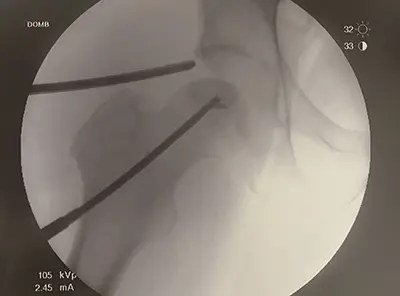

- Core Decompression: A portion of the inner bone is removed to relieve pressure, encourage blood vessel growth, and stimulate new bone formation. In the hip, this is often done through the neck of the femur to the femoral head and can be assisted arthroscopically.

Dr. Domb and his team often perform AVN treatment using an arthroscopic-assisted approach, which allows for:

- Minimally invasive surgery with smaller incisions

- Direct visualization of the cartilage in the femoral head before performing core decompression

- Precise targeting of the decompression to the affected area

- Safe placement of bone grafts or orthobiologics without entering the joint space

- Simultaneous treatment of other hip issues, such as labral tears or impingement

This approach helps patients preserve their hip joint and improves recovery outcomes while addressing multiple hip issues at once.